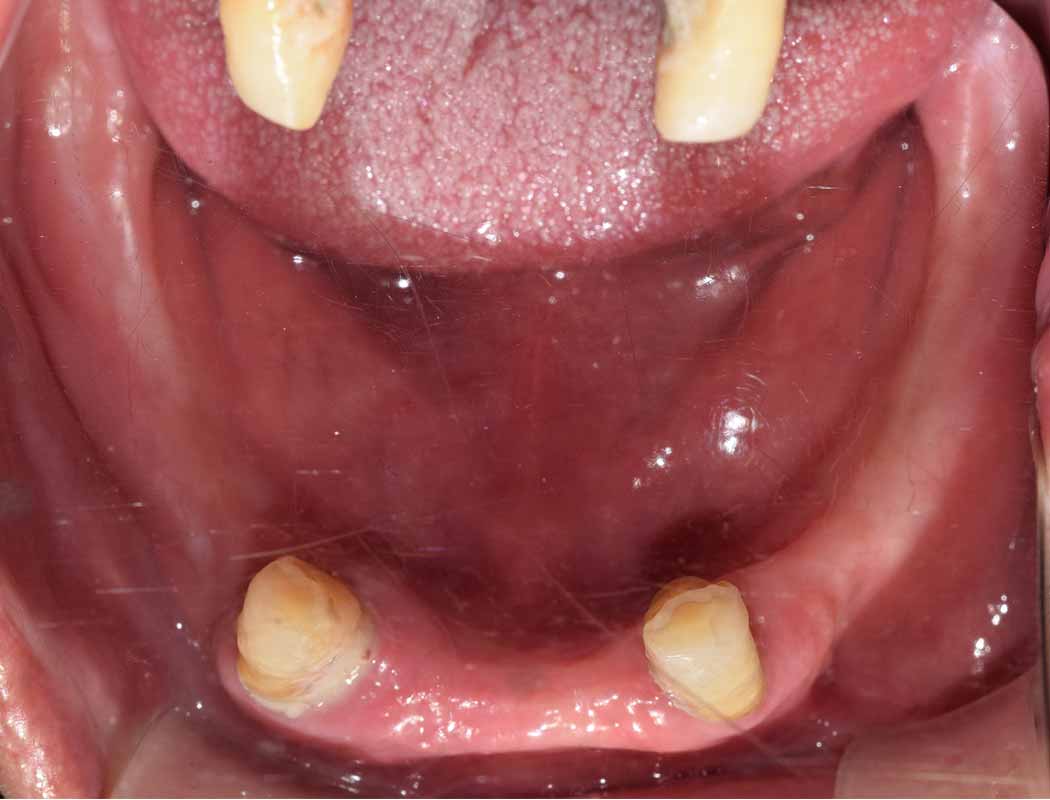

전후 수술 예시 사례

드림연합치과는 환자 중심 자연치아의 보존을 최우선으로 하며, 임플란트는 신중히 고려된 대안으로만 제안됩니다.

그러나 일상생활이 어려운 환자들을 위해, 풍부한 대학 병원 임상경험을 바탕으로 양한 임플란트 케이스에 대한 경험을 보유하고 있습니다.

우리의 목표는 단순한 치아 대체가 아닌, 환자의 삶의 질 향상입니다.

이미지 위에 가운데 동그라미를 클릭한 상태에서 왼쪽 또는 오른쪽으로 드래그해보세요! 드래그할 때마다 환자의 전후 변화를 확인하실 수 있습니다.

전체 임플란트 전 후 실제 사례

전체 임플란트 환자 사례 #1

전체 임플란트 환자 사례 #2

🦷 전체 임플란트 수술 전 후 Case 1

🦷 전체 임플란트 수술 전 후 Case 2